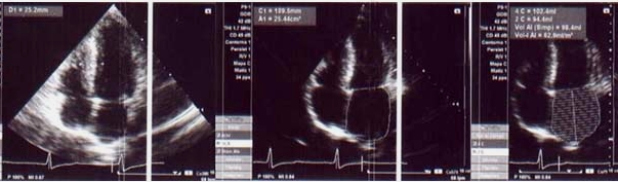

Con los signos y síntomas de la prueba ergométrica y las imágenes obtenidas en el SPM, se plantea el diagnóstico de miocardiopatía hipertrófica con severa obstrucción dinámica del tracto de salida. Se indica tratamiento con beta bloqueantes, comenzándose con bajas dosis por cifras de PA basal de 110/60 mmHg y se suspende la actividad física deportiva o ejercicios intensos. Se solicita nuevo ecodoppler cardíaco (fig. 5) dada la discordancia de estos hallazgos con el resultado del primer estudio ecocardiográfico.

Con el resultado del nuevo ecocardiograma que confirma la presunción diagnóstica, determinando la existencia de una obstrucción pico de 100 mmHg en reposo, a pesar del tratamiento instaurado (que por otra parte tampoco produjo mejoría subjetiva), se indica a la paciente tratamiento quirúrgico mediante miomectomía septal estando a la espera del procedimiento. En suma, se trata de una miocardiopatía hipertrófica obstructiva severamente sintomática y con signos de alto riesgo.